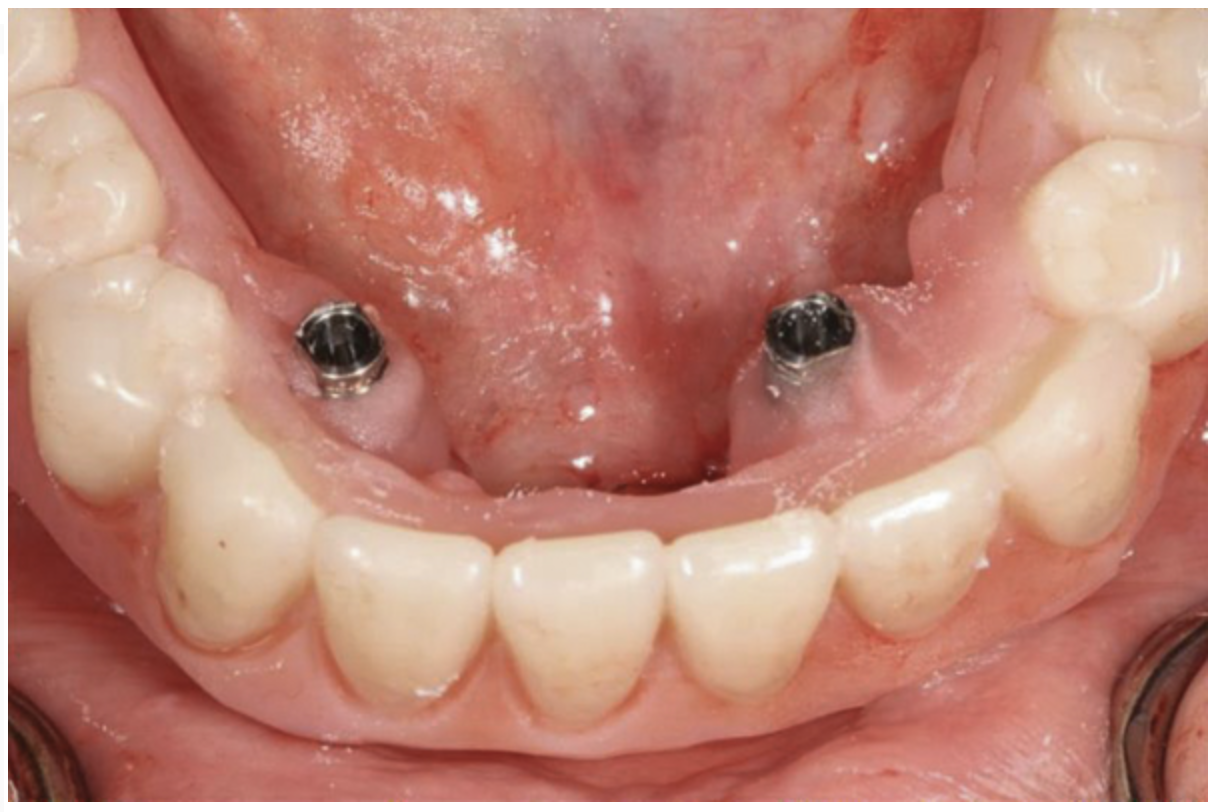

Fig 20. Patient intraoral condition 3 years following delivery of maxillary and mandibular All-on-4 definitive prosthesis.

Figure 20